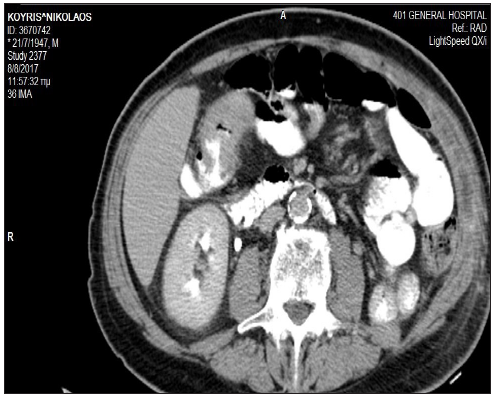

A 69 years-old male, smoker, with a past history of hypertension, depression, benign prostatic hyperplasia, and hypercholesterolemia, presented with macroscopic hematuria and weight loss. Computed tomography scans revealed a left renal mass, bilateral pulmonary nodules, and thickening of the hepatic flexure colon mass. Patient underwent a left nephrectomy and the histopathological examination confirmed the presence of a grade 3, pT3Nx, clear-cell carcinoma. Colonoscopy identified a mass in the transverse colon covering three quarters of the lumen and the histological report confirmed the presence of a moderately differentiated invasive colon adenocarcinoma (Figure 1). Post surgery CT scans revealed deterioration of the known pulmonary lesions and presence of a new left pleural effusion (Figure 2a) together with a hepatic flexure colon mass (Figure 2b). A CT-guided lung lesion biopsy was consistent with RCC metastatic disease. In view of the asymptomatic colon cancer and the rapidly imaging deterioration of the metastatic renal cancer, treatment with pazopanib commenced with acceptable toxicity and partial response of both the renal metastatic disease and the colonic primary tumor. After eight months of treatment, imaging tests revealed disease progression in the lung, while the colon mass was further responding. Second-line treatment with axitinib commenced and the restaging CT scans, after 10 months from initial diagnosis, were consistent with a new partial response of metastatic disease (Figure 3a & 3b), while a new colonoscopy revealed complete remission of the colon cancer. Treatment with axitinib continued for 5 months overall, with good tolerance. The patient presented brain and leptomeningeal metastatic disease with rapid clinical deterioration and succumbed 15 months after initial diagnosis.

Figure 3a A baseline abdomen CT scan showing thickening of the transverse colon.